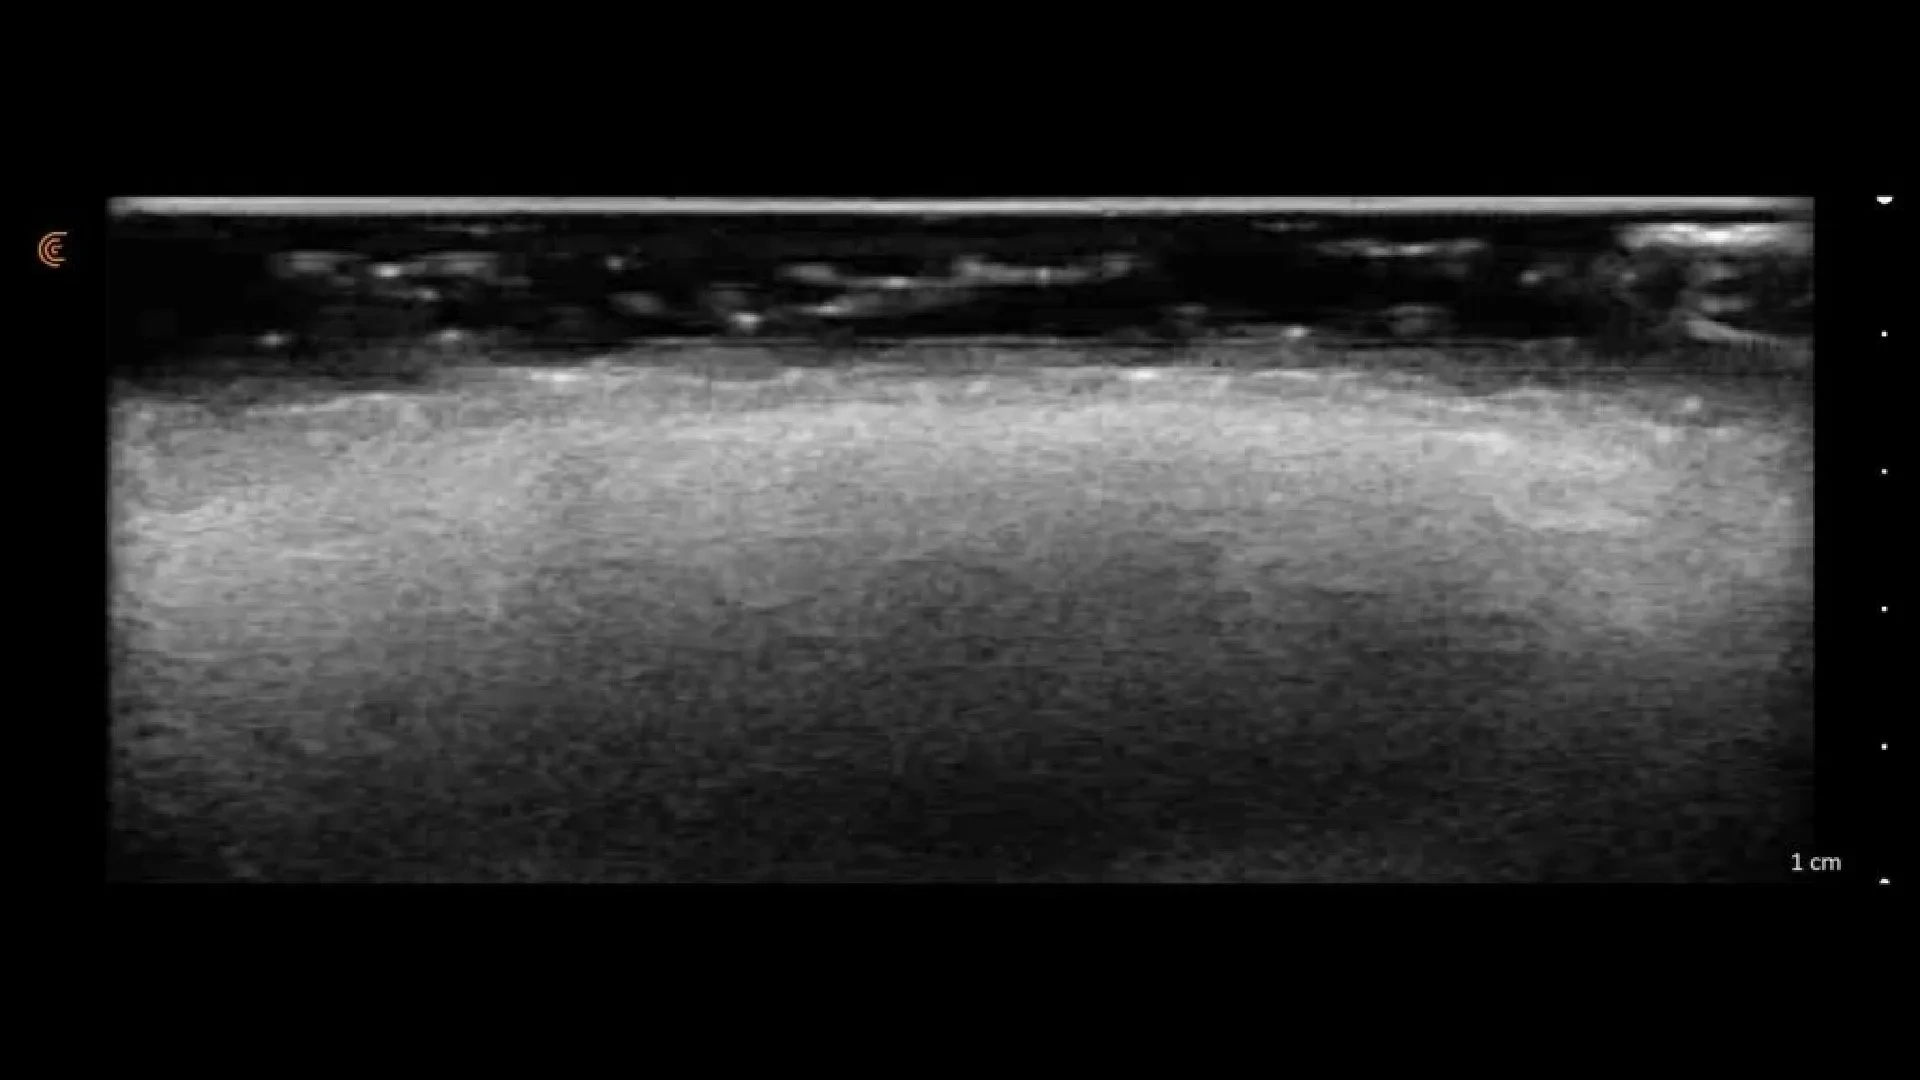

A diferencia de los métodos tradicionales, NesAI utiliza algoritmos de deep learning para analizar imágenes ecográficas en tiempo real. Esto permite:

- Mapeo vascular de alta precisión: Localiza arterias y venas críticas para realizar infiltraciones con riesgo cero de complicaciones vasculares.

La valoración inicial comienza con un análisis profundo de la anatomía y las necesidades del paciente. Durante esta fase, realizamos una entrevista clínica detallada para conocer antecedentes y tratamientos previos. El punto diferencial es el uso de la IA de NesAI, que nos permite realizar una ecografía facial avanzada para mapear estructuras internas, localizar rellenos antiguos y detectar vasos sanguíneos críticos.

El desarrollo de la sesión se lleva a cabo bajo los más estrictos protocolos de seguridad y confort. Tras la limpieza y el marcaje de precisión basado en el mapa ecográfico previo, se procede a la ejecución del tratamiento (ya sea infiltración, cirugía o láser). Gracias a la información obtenida por la inteligencia artificial, podemos actuar exactamente en el plano anatómico deseado, minimizando riesgos y optimizando el resultado